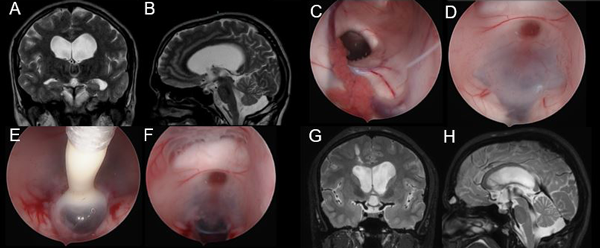

Se presentan en figuras 8 a 12 los casos ilustrativos más representativos de nuestra serie.

Figura 8: Hidrocefalia en contexto de germinoma gigante supra e infratentorial: A-B) RM preoperatoria. C-F) Hallazgos intra-operatorios. G-H) RM cerebral postoperatoria.

Figura 9: Hidrocefalia en contexto de subestenosis acueductal por metástasis de cáncer de mama: A-B) RM preoperatoria. C-F) Hallazgos intra-operatorios, nótese la hidro disección del foramen de Monro cerrado. G-H) RM cerebral postoperatoria.

Figura 10: Hidrocefalia post infecciosa A-B) RM preoperatoria. C-F) Hallazgos intra-operatorios. G-H) RM cerebral postoperatoria.

Figura 11: Hidrocefalia por obstrucción de la salida del IV ventrículo por quiste de Blake A-B) RM preoperatoria. C-F) Hallazgos intra-operatorios. G-H) RM cerebral postoperatoria.

Figura 12: Hidrocefalia en contexto de malformación de vena de Galeno. Paciente con válvula previa, se ingresa por izquierda: A-B) RM preoperatoria. C-F) Hallazgos intra-operatorios. G-H) RM postoperatoria.